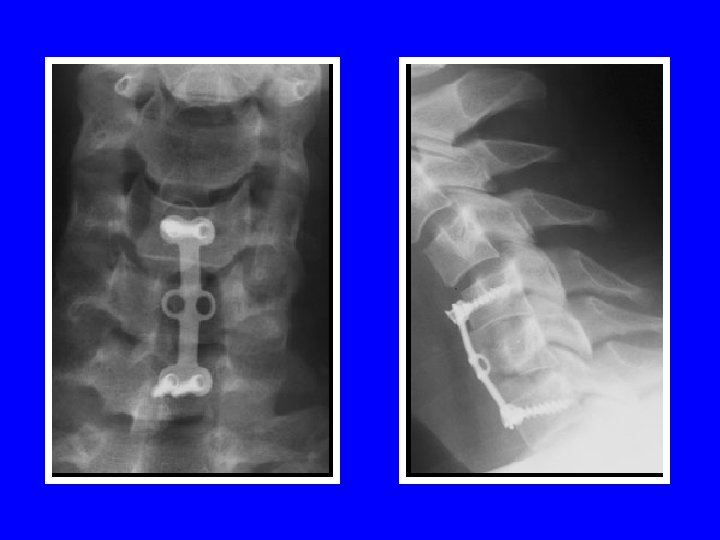

STABILISATION DU RACHIS VOIE ANTERO-LATERALE (Smith et Robinson) stabilisation par greffe autologue + ostéosynthèse par plaque vissée dans les corps VOIE POSTERIEURE (Roy-Camille) stabilisation par plaques vissées dans les massifs articulaires stabilisation par crochets lamaires stabilisation par laçage interlamaire

VOIE ANTERO-LATERALE

VOIE POSTERIEURE